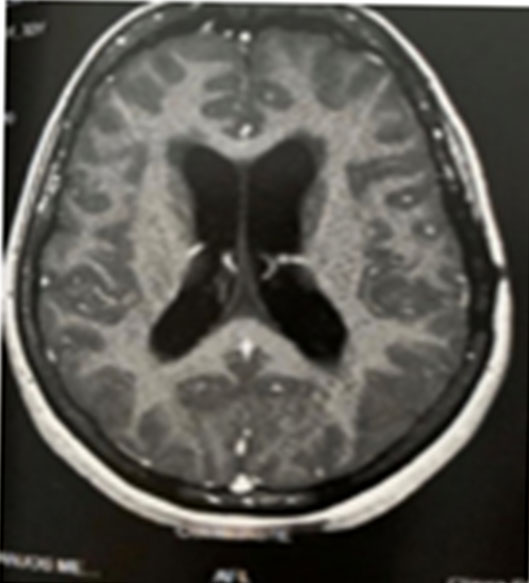

The patient remained stable for eight months, but in March 2020, headaches, visual disturbance, and paresthesia in the body relapsed. Results of MRI showed two new lesions on the brain, and the MRI spectroscopy suggested that they were granulomatous lesions with reactional edema (Figure 5). A new therapeutic RIPE regimen was prescribed, with larger doses. She continues being followed up by our team.

Figure 5: (A) Magnetic resonance imaging showing two new lesions on the brain. (B) Magnetic resonance spectroscopy suggesting granulomatous lesions with reactional edema.

Share Image: